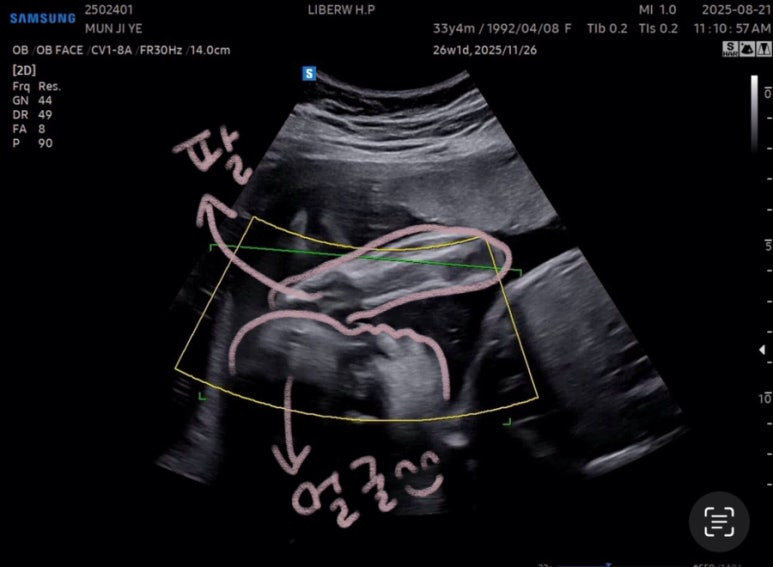

오랜만에 본 사탕이는

머리가 밑으로 잘 이동해있었다😊

27주차 사탕이는

머리둘레 6.62cm

배 둘레 22.91cm

다리길이 4.61cm

몸무게 956g

심장박동수 150bpm

경부길이 3.44cm

양수량도 적당했다

잘 체크하고 드디어 얼굴을 보는 시간!!

아쉽게도

사탕이는 얼굴을 가리고 있었다🥲

안쪽에 팔로 얼굴 가리고 숨은 사탕

이 상태로 찍어봤지만,,,!

여기까지가 최선이었다^^,,,